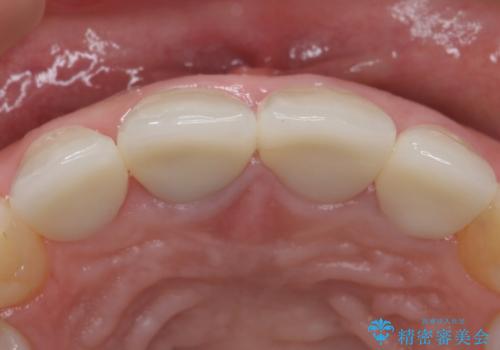

歯ぐきの炎症を抑えつつ、被せ物と歯との境目がわからなくなるよう被せ物を装着しました。

審美性が大変改善されたことで患者様にもご満足いただけました。